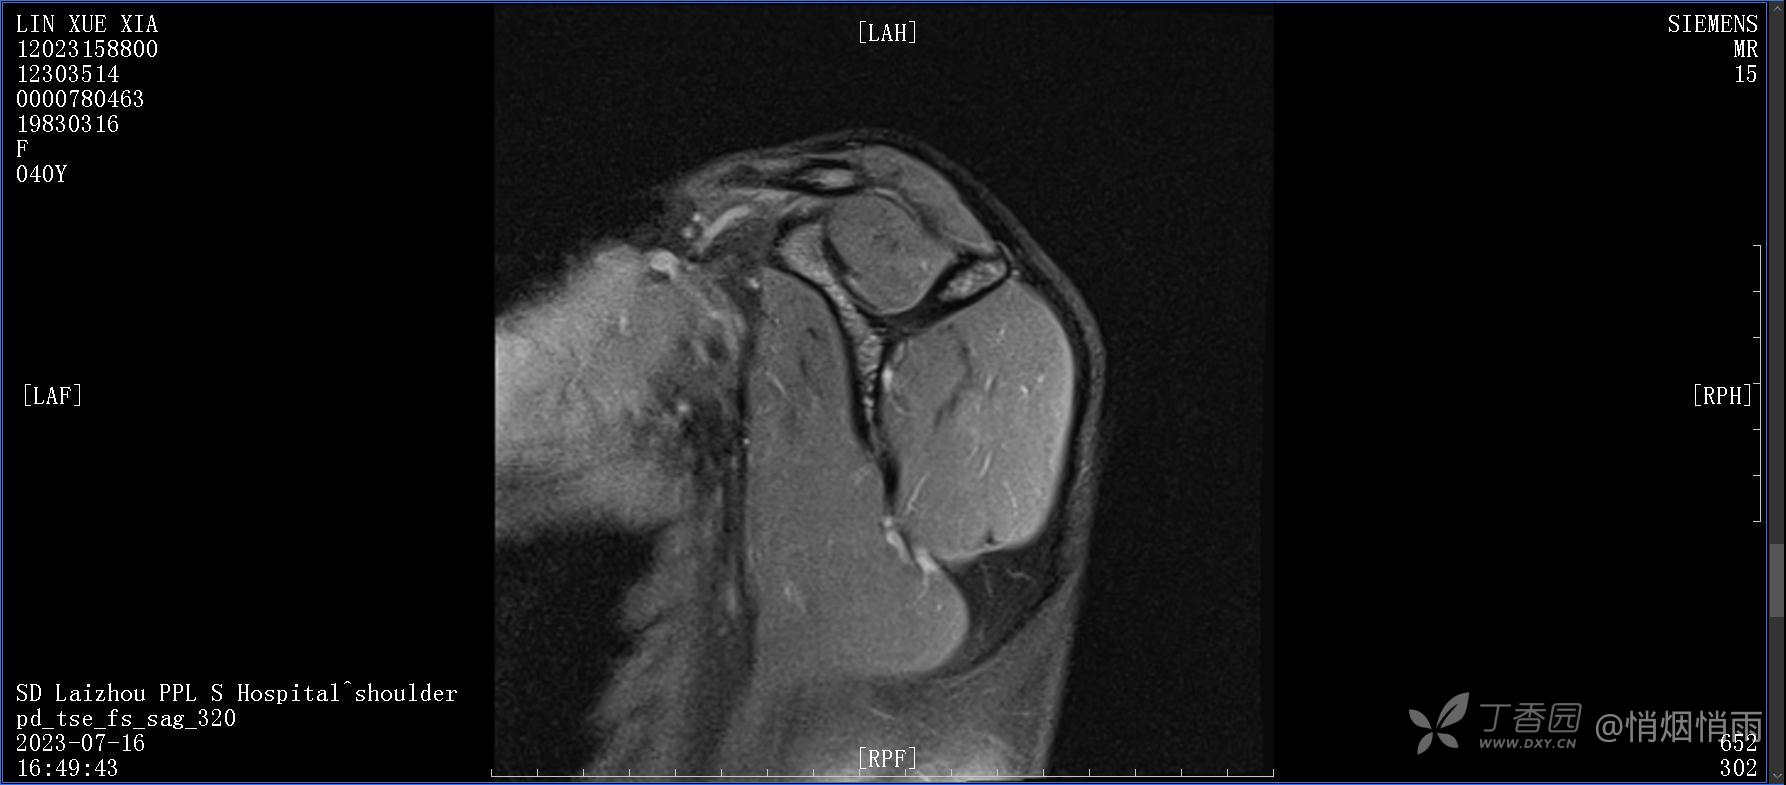

查体:右肩关节局部轻度肿胀,肩胛区压痛明显,痛处不固定,肩关节痛性活动受限,jobe test(+),lift -off test(+),中指、环指感觉较余指减退,余肢端感觉及血运情况可。

目前的诊断,暂时依据辅助检查诊为肩袖损伤,但是患者疼痛的性质和特点,却不是单纯的肩袖损伤所致。考虑过胸廓出口综合征,但是该疾病会出现肩胛区的疼痛吗?(由于考虑到费用的问题,没再进行下一步的检查)带状疱疹会有如此的症状吗?